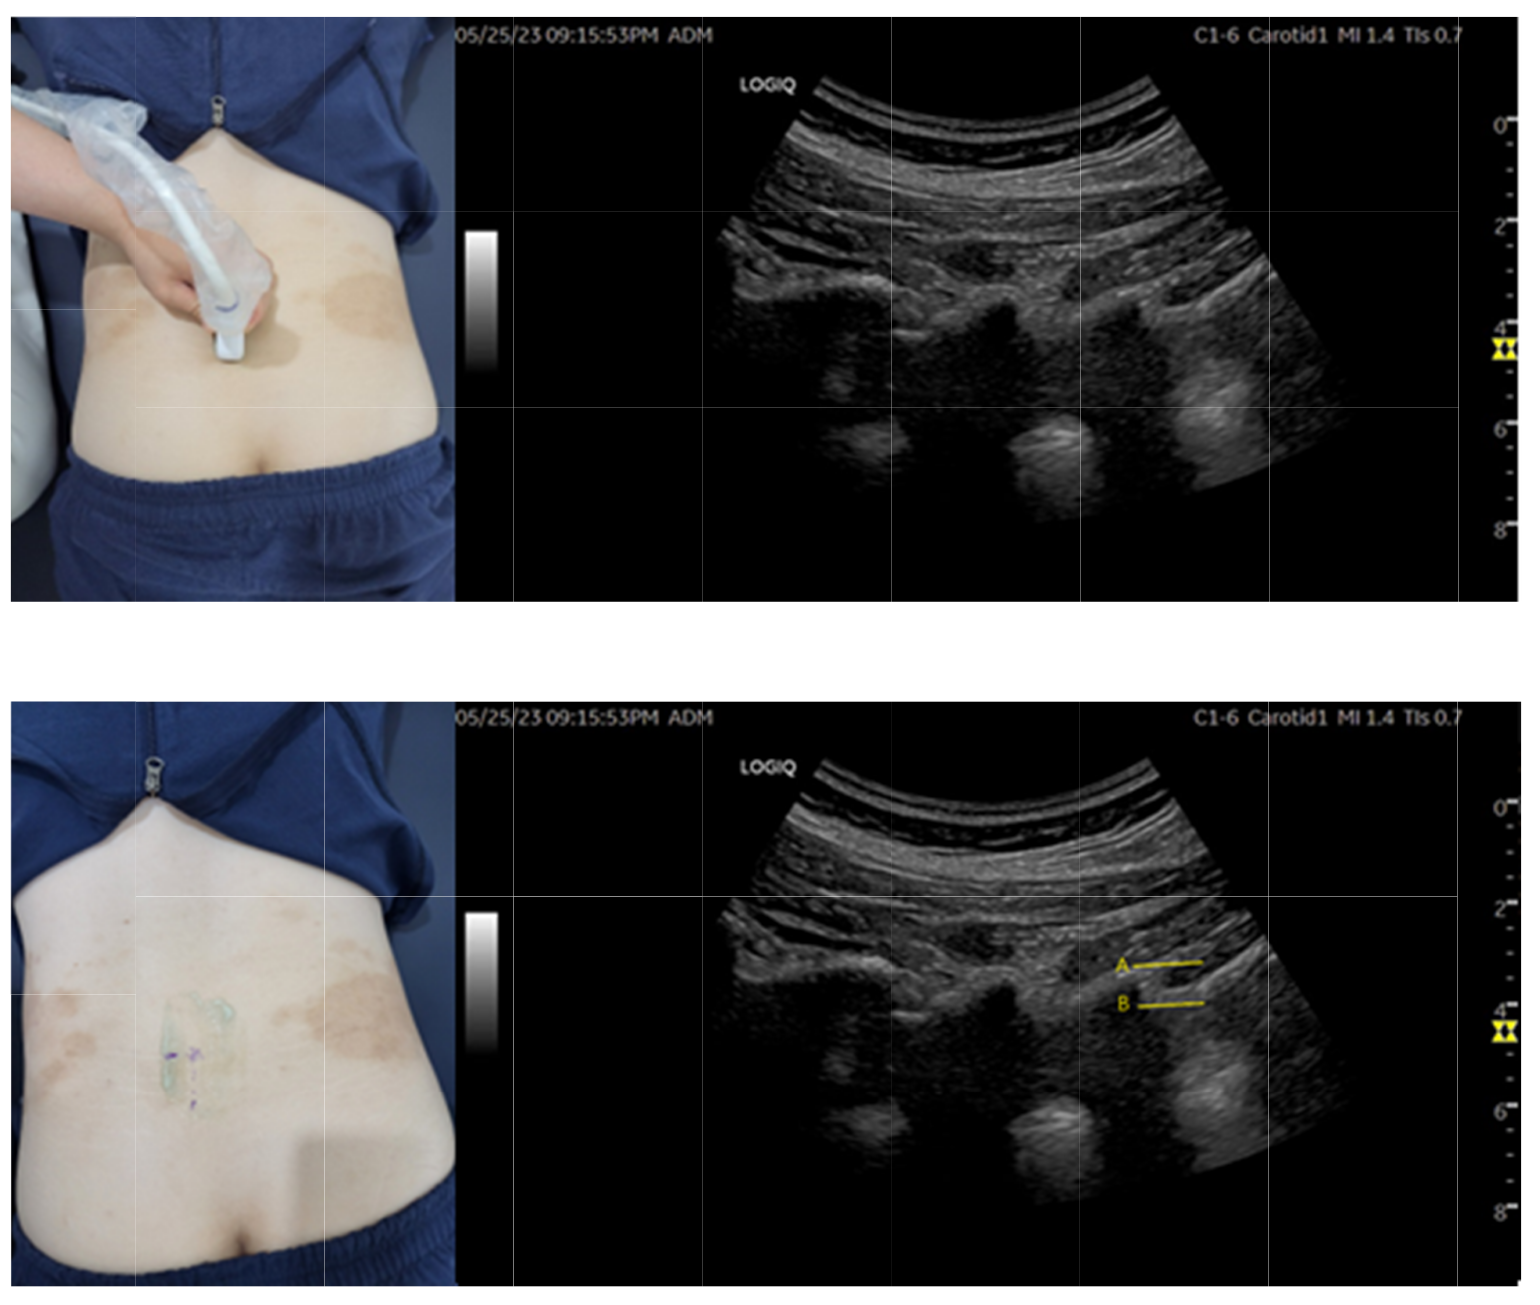

◇ 직접 중재술(초음파 중재 하 내구혈취혈 방법)

① 장축으로 초음파를 환자 허리에 대고 Neuroaxial view 중 Lamina view에서 시술하려는 레벨을 선정한다.

② 시술하려는 레벨에서 프로브를 안쪽으로 기울여 Inter-laminal space가 보이도록 초음파를 주사한다.

③ 침도 자입 시 Probe의 간섭을 피하기 위해 초음파에서 1cm 정도 떨어진 위치의 수평면상에서 15도 정도 침도를 기울여 자입한다.

④ 시술하려는 레벨의 위 라미나의 상단에서 하단 사이를 목표로 초음파상에서 진입경로를 확인한다.

⑤ 에피듀라에 진입하지 않고, 황색인대를 안전 자극할 수 있는 골표지자(Bone turnover marker)는 위 라미나의 하단과 아래 라미나의 상단 사이다.

⑥ 시술 목표에 따라 황색인대를 Epidural space에 진입하지 않는 선에서 초음파 중재 하에 절개한다.

연구진은 이때 가장 주의할 점으로 경막 자극 및 경막 천공 손상을 꼽았는데, 경막 자극을 피하기 위해선 황색인대 침도 시술 시 완전히 관통시키지는 않아야하며, 이를 위해 자입심도를 초음파로 확인해 해당 깊이 이상 침도를 진침 시키지 않도록 권고했다.